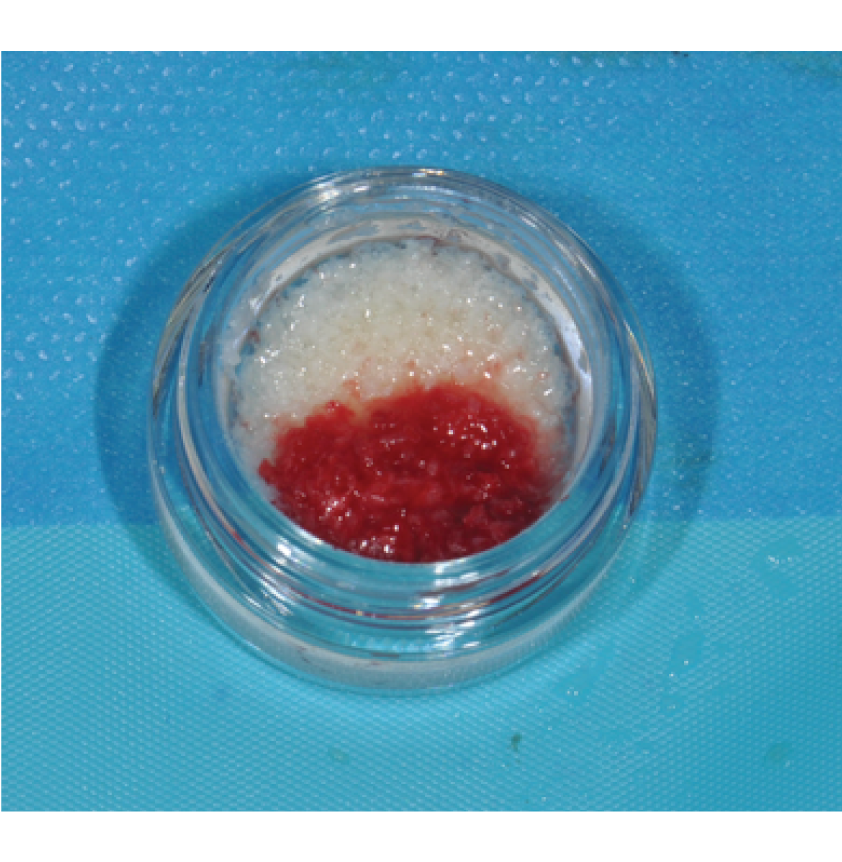

Director’s Clinical Cases

Director’s Clinical Cases

• Biomaterials overview: Allografts, Xenografts, Autografts and Alloplasts

• Biomaterials overview: Allografts, Xenografts, Autografts and Alloplasts